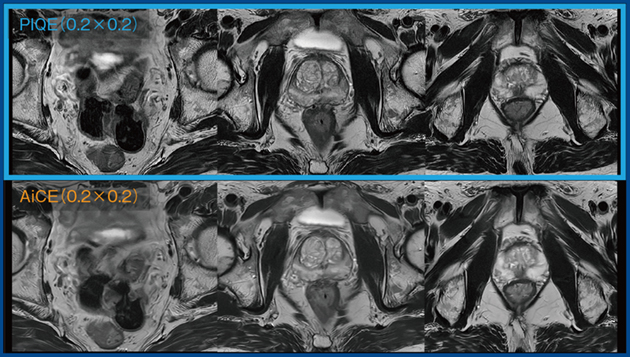

前立腺MRIの撮像はPI-RADSに準拠して行うが,推奨条件が厳しく,表面コイルを用いた撮像ではSNRが不十分となる。AiCEを適用すればSNRは改善するものの撮像時間は4分以上かかるが,PIQEを適用して周波数方向のマトリクスサイズやバンド幅,エコースペース,SPEEDER factorなどを調整することで,SNRを維持しつつ,撮像時間を3分以下に短縮できる。そのため,当院では現在,前立腺MRIのT2WIおよびDWIのすべてにPIQEを適用している。図6は実際の画像であるが,PIQEの適用によって,腸管のモーションアーチファクトが低減し,前立腺の内腺や外腺のコントラストもより明瞭になっている。

図6 AiCEとPIQEを用いた前立腺T2WI